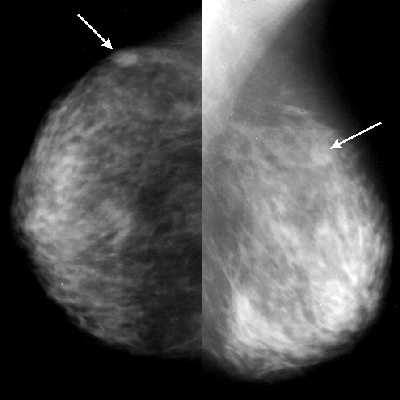

УЗИ молочных желез — информативный и безопасный метод диагностики, с помощью которого можно точно оценить состояние желез, обнаружить доброкачественные и злокачественные образования, уточнить диагноз. Это доступное по цене исследование безвредно и не несет лучевой нагрузки. Оно имеет большое значение в ранней диагностике заболеваний и нередко применяется в профилактических целях. На УЗИ может направить маммолог, онколог, эндокринолог, гинеколог.

Сделать УЗИ молочных желез можно в качестве первичной диагностики и для уточнения уже предполагаемого диагноза. Метод основывается на способности высокочастотных ультразвуковых волн с различной скоростью отражаться от тканей с разной плотностью.

С помощью ультразвуковой диагностики можно обнаружить следующие заболевания:

- воспалительные заболевания — мастит, абсцессы, лактостаз у кормящих женщин, мастопатии различного происхождения и типа — фиброзно-кистозные, диффузные и пр.;

- врожденные аномалии молочной железы;

- рак;

- кисты и доброкачественные опухоли;

Кому противопоказано

УЗИ практически не имеет противопоказаний. Однако важно отметить, что информативность обследования груди таким способом у женщин молодого возраста выше, поскольку ткани молочных желез с возрастом становятся более рыхлыми. Поэтому после 40 лет УЗИ в большинстве случаев сочетается с рентген-диагностикой (маммографией).